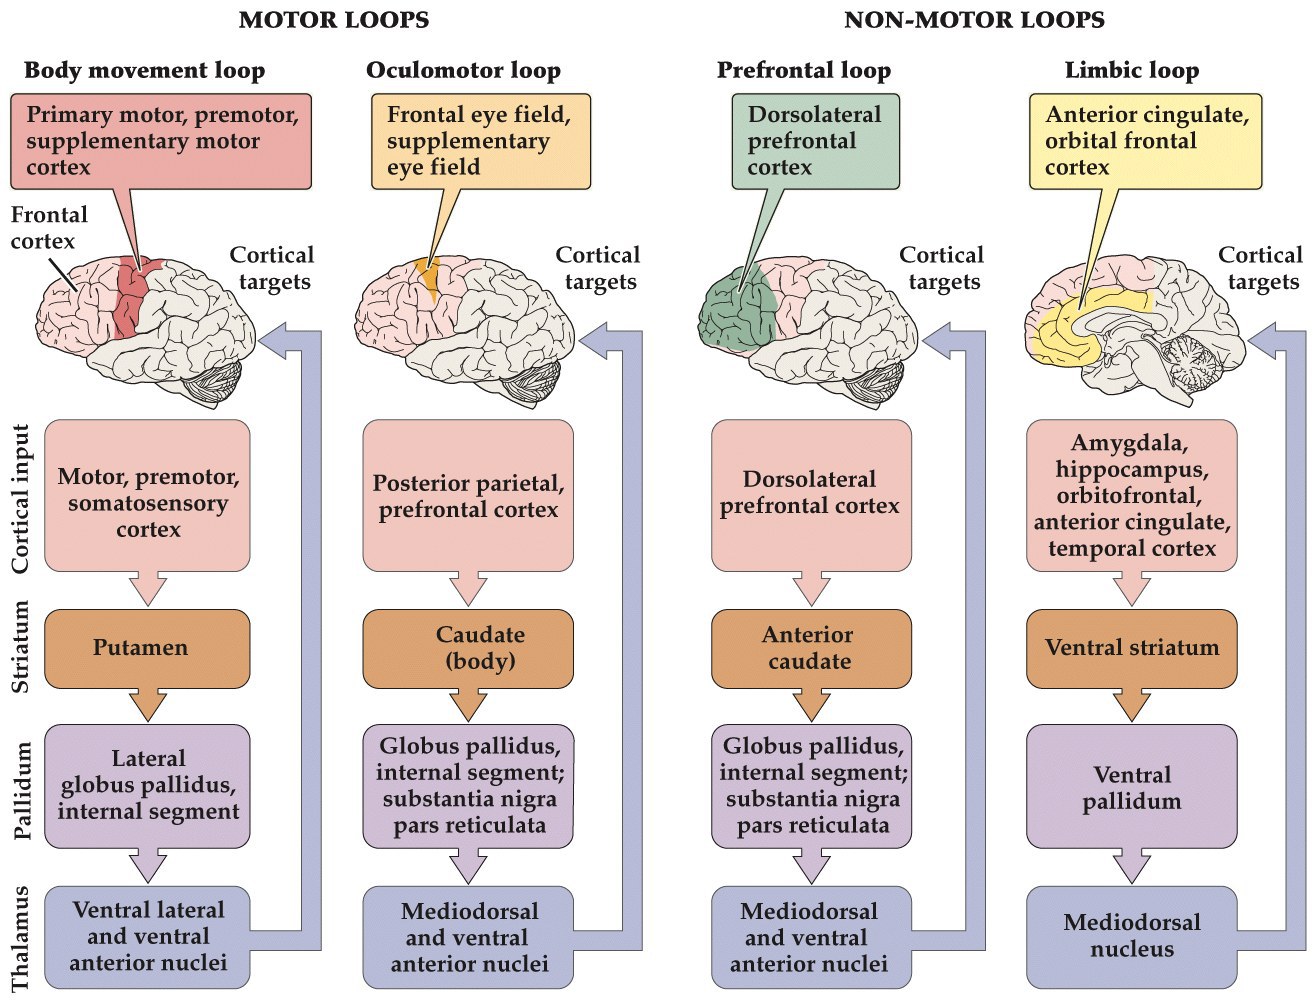

Non-motor loops of the basal ganglia

- Basal ganglia are also involved in loops that modulate non-motor behaviors

- Work in a similar way to suppress outputs

- The limbic loop regulates emotional behavior and motivation

- Tourette’s may be a problem with limbic loop (no longer have inhibitions with language selection?)

- Drugs of abuse affect dopamine release

- Schizophrenia, may be due to aberrant activity in limbic and prefrontal loops resulting in hallucinations disordered cognition

prefrontal loop may regulate initiation and termination of cognitive processes like planning, working memory, attention

-

limbic loop could initiate and terminate emotional and motivated behavior, transitions from one mood state to another

-

deterioration of cognitive and emotional function in Parkinson's and Huntington's disease may be result of disruptions to these non-motor loops

antipsychotic drugs that act on dopaminergic receptors support hypothesis that schizophrenia involves disruption of basal ganglia non-motor loops

drugs of abuse that affect dopamine neurotransmission

Types of corticostriatal loops

Tourettes may be a disruption to non-motor corticostriatal loops.